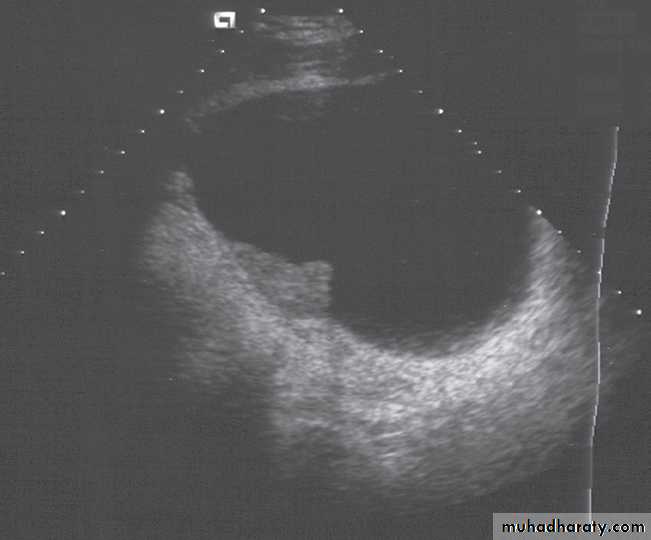

The bladder is the most frequent site for neoplasms in the urinary tract . Almost all are transitional cell carcinomas of varying degrees of malignancy.On ultrasound examination

bladder tumours are seen as soft tissue masses protruding into the fluid-filled bladder or as localized bladder wall thickening, . On rare occasions, there is visible calcification on the surface of the tumour, but the technique is poor for detecting extravesical spread.

On CT and MRI, a bladder tumour is seen as a soft tissue mass projecting from the wall or a focal thickening of the bladder wall . As the diagnosis is best established by cystoscopy and biopsy, the roles of CT and MRI are to stage the tumour. CT and MRI can determine the spread of tumour beyond the bladder wall and assess lymph node involvement .